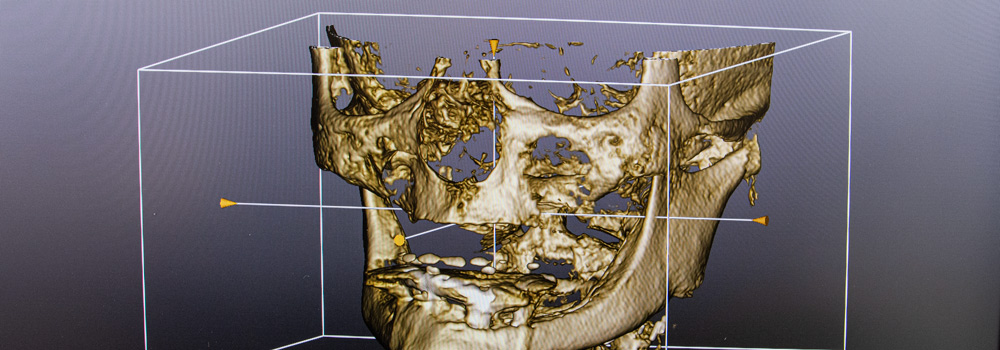

Die Qualität unserer Produkte garantieren wir durch manuelle Präzision mit digitaler Hilfe.

Alle unsere Produkte sind zu 100% in Winterthur gefertigt. Mit Materialien und Maschinen aus der Schweiz und der EU.